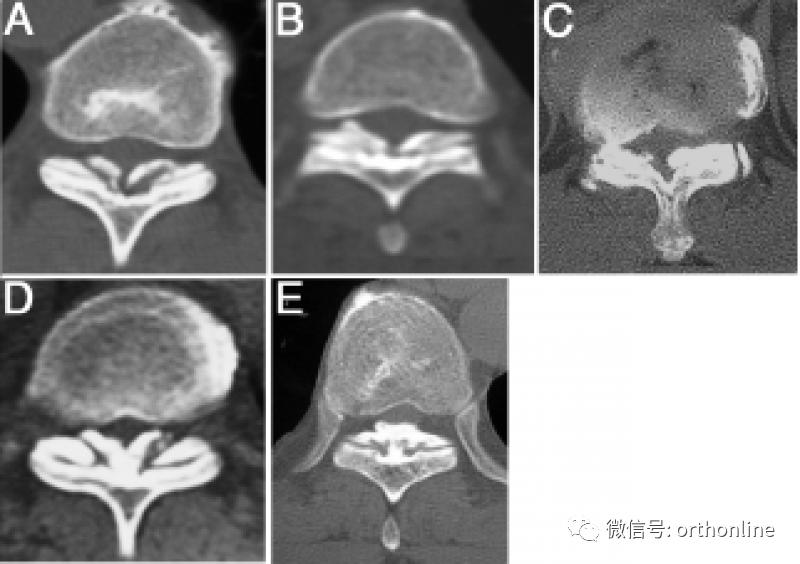

1.CT分型:按照轴位CT分为外侧型、延展型、肥厚型、融合型、结节型。

A.外侧型(Lateral type):黄韧带囊部骨化,骨化物位于椎管外侧缘;

B.延展型(Extended type):椎板间部黄韧带骨化;

C.肥厚型(Enlarged type):黄韧带骨化侵及椎管内,但中线未融合;

D.融合型(Fused type):双侧黄韧带骨化融合于椎管中线,但中线尚可见凹型切面;

E.结节型(Tuberous type):双侧黄韧带骨化融合并形成骨化结节凸向椎管内。